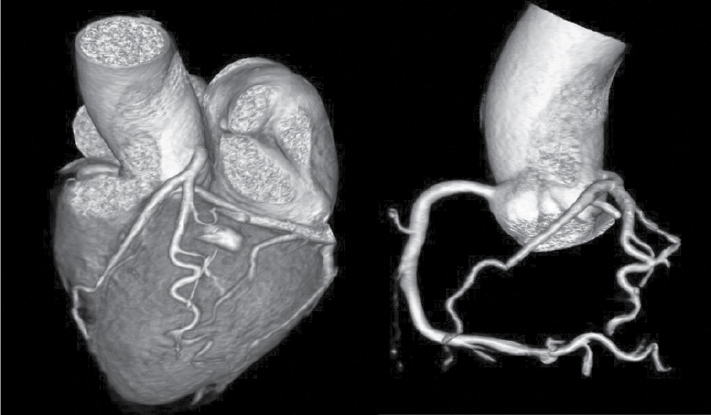

At Nizam’s Institute of Medical Sciences (NIMS), Hyderabad, 770 patients underwent CT-conventional coronary angiography (CAG), on 128-slice single source MDCT (SOMATOM Definition AS ± SEIMENS) during the last 3 years (unpublished data). On analysis, coronary artery anomalies were found in 23 patients (3%). Their ages ranged from 25 to 82 years. Majority of the cases were in 51 to 60 years age group. Among them, 17 were males. The most common anomaly seen was high take-off of coronary arteries, seen in 10 cases. Of them, 2 were having high origin of right coronary artery (RCA) (Fig. 1), 7 were having high origin of left main coronary artery (LMCA) and one was having high origin of both coronary arteries with acute kink at the origin of RCA. Anomalous origin of coronary artery from opposite sinus was seen in 8 cases (Figs. 2-5). RCA from left coronary sinus with interarterial course between aorta and right ventricular outflow tract was seen in 5 cases. Anomalous origin of left coronary artery (LCA) from right coronary sinus with interarterial course between aorta and right ventricular outflow tract was seen in 2 cases. Anomalous origin of left circumflex artery (LCx) from right coronary sinus with retroaortic course was seen in 1 case (Fig. 6). Separate ostia for left anterior descending artery (LAD) and LCx was noted in 3 patients (Figs. 7 and 8). Shepherd crook deformity of proximal segment of RCA was seen in 1 patient. Super-dominant RCA with absent LCx was seen in 1 patient (Fig. 9).

Figure 1. Two different patients of ‘high take-off’ of LCA in patient aged 61/M and RCA in patient aged 58/M.